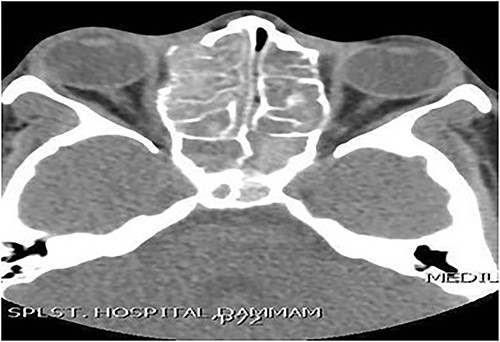

A 8-year-old female with known bronchial asthma presented with right nasal obstruction & mild right eye proptosis for 9 months. Endoscopic nasal examination showed multiple right nasal polyps. CT scan of the paranasal sinuses (Fig. 4) and FESS confirmed the diagnosis of right-sided allergic fungal pansinusitis. After 3 years, she presented with left-sided nasal obstruction & discharge. Upon performing the endoscopic nasal examination, multiple nasal polyps were found in the left nose. CT scan of the paranasal sinuses (Fig. 5) confirmed the diagnosis of left-sided allergic fungal pansinusitis, but the operated right-sided sinuses were normal. The child remained symptoms-free for 5 years follow-up.

Coronal CT paranasal sinuses shows heterogeneous opacities filling the right frontal sinus with extension through the right frontal recess. It involves the ethmoid sinus with expansion. The right lamina papyracea shows lateral displacement with partial dehiscence and nasal polyposis.